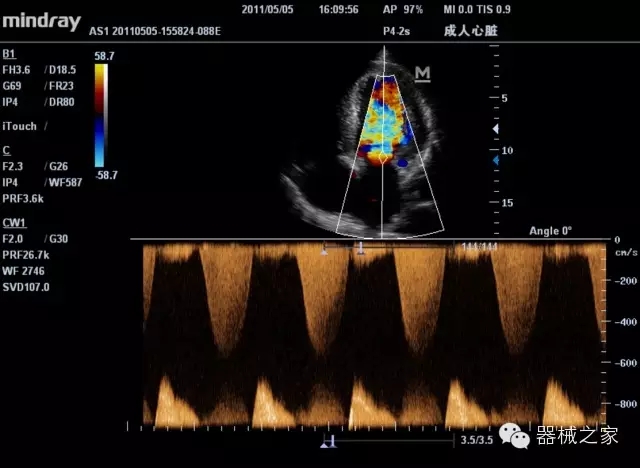

臨床圖片賞析

產(chǎn)品特點(diǎn)

·裝載有采用Multi-Core多核處理的非嵌入式平臺(tái),成像效率大大提高,并且能夠給用戶帶來(lái)高速、多任務(wù)并行信號(hào)處理體驗(yàn);

·優(yōu)秀的圖像效果、強(qiáng)大的功能體驗(yàn)、豐富的探頭選擇、合理的便攜式設(shè)計(jì),全中文顯示及病人管理界面,使得M7在任何場(chǎng)合、任何時(shí)候都能快速響應(yīng)更好的心血管、腹部、婦產(chǎn)、小器官等常規(guī)超聲檢查以及肌骨、神經(jīng)、顱腦、術(shù)中等新興領(lǐng)域的使用需求;

8倍波束并行處理系統(tǒng)

·在便攜式緊湊平臺(tái)上采用更多倍波束并行接收信號(hào)處理模式,無(wú)論二維還是彩色血流圖像狀態(tài)下,擁有更靈敏的回波頻移捕獲能力,大大提高時(shí)間分辨率,尤其使得心血管表現(xiàn)更為突出;